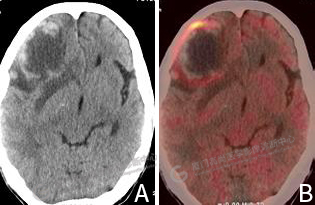

圖2:A CT圖像,右側(cè)額葉見一混雜密度腫塊影,形態(tài)欠規(guī)則,其內(nèi)伴低密度壞死區(qū)。B PET/CT融合圖像,病灶邊緣局限性代謝增高。

雙肺見多發(fā)結(jié)節(jié)影,大者位于左肺下葉外基底段,大小約0.9×0.8cm,F(xiàn)DG攝取明顯增高,SUVmax 7.7。右側(cè)額葉見一混雜密度腫塊影,大小約5.1×4.1cm,形態(tài)欠規(guī)則,其內(nèi)密度不均,伴低密度壞死區(qū),邊緣見斑片、條片狀高密度影,實(shí)質(zhì)部分FDG攝取呈環(huán)形增高,SUVmax 8.3,周圍見片狀水腫帶(圖2)。